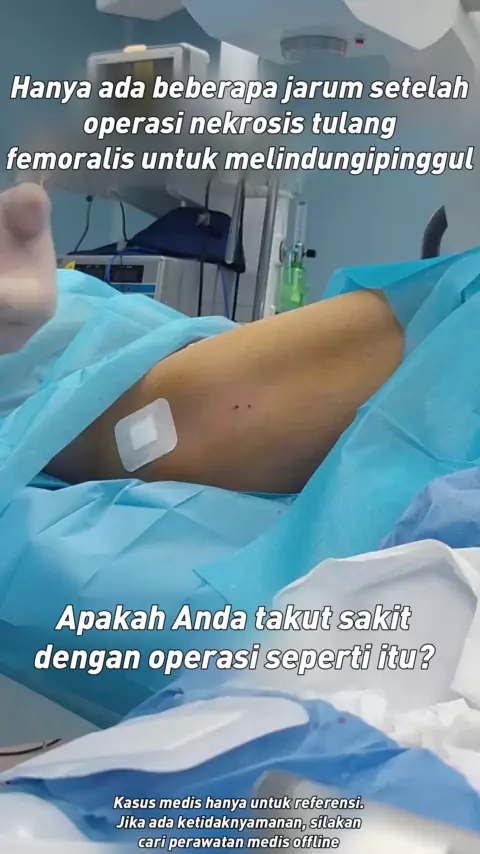

Hanya ada beberapa jarum yang tersisa setelah operasi pinggul. Apakah Anda takut sakit dengan operasi seperti itu? # femur nekrosis # kesehatan # Ruang operasi setiap hari